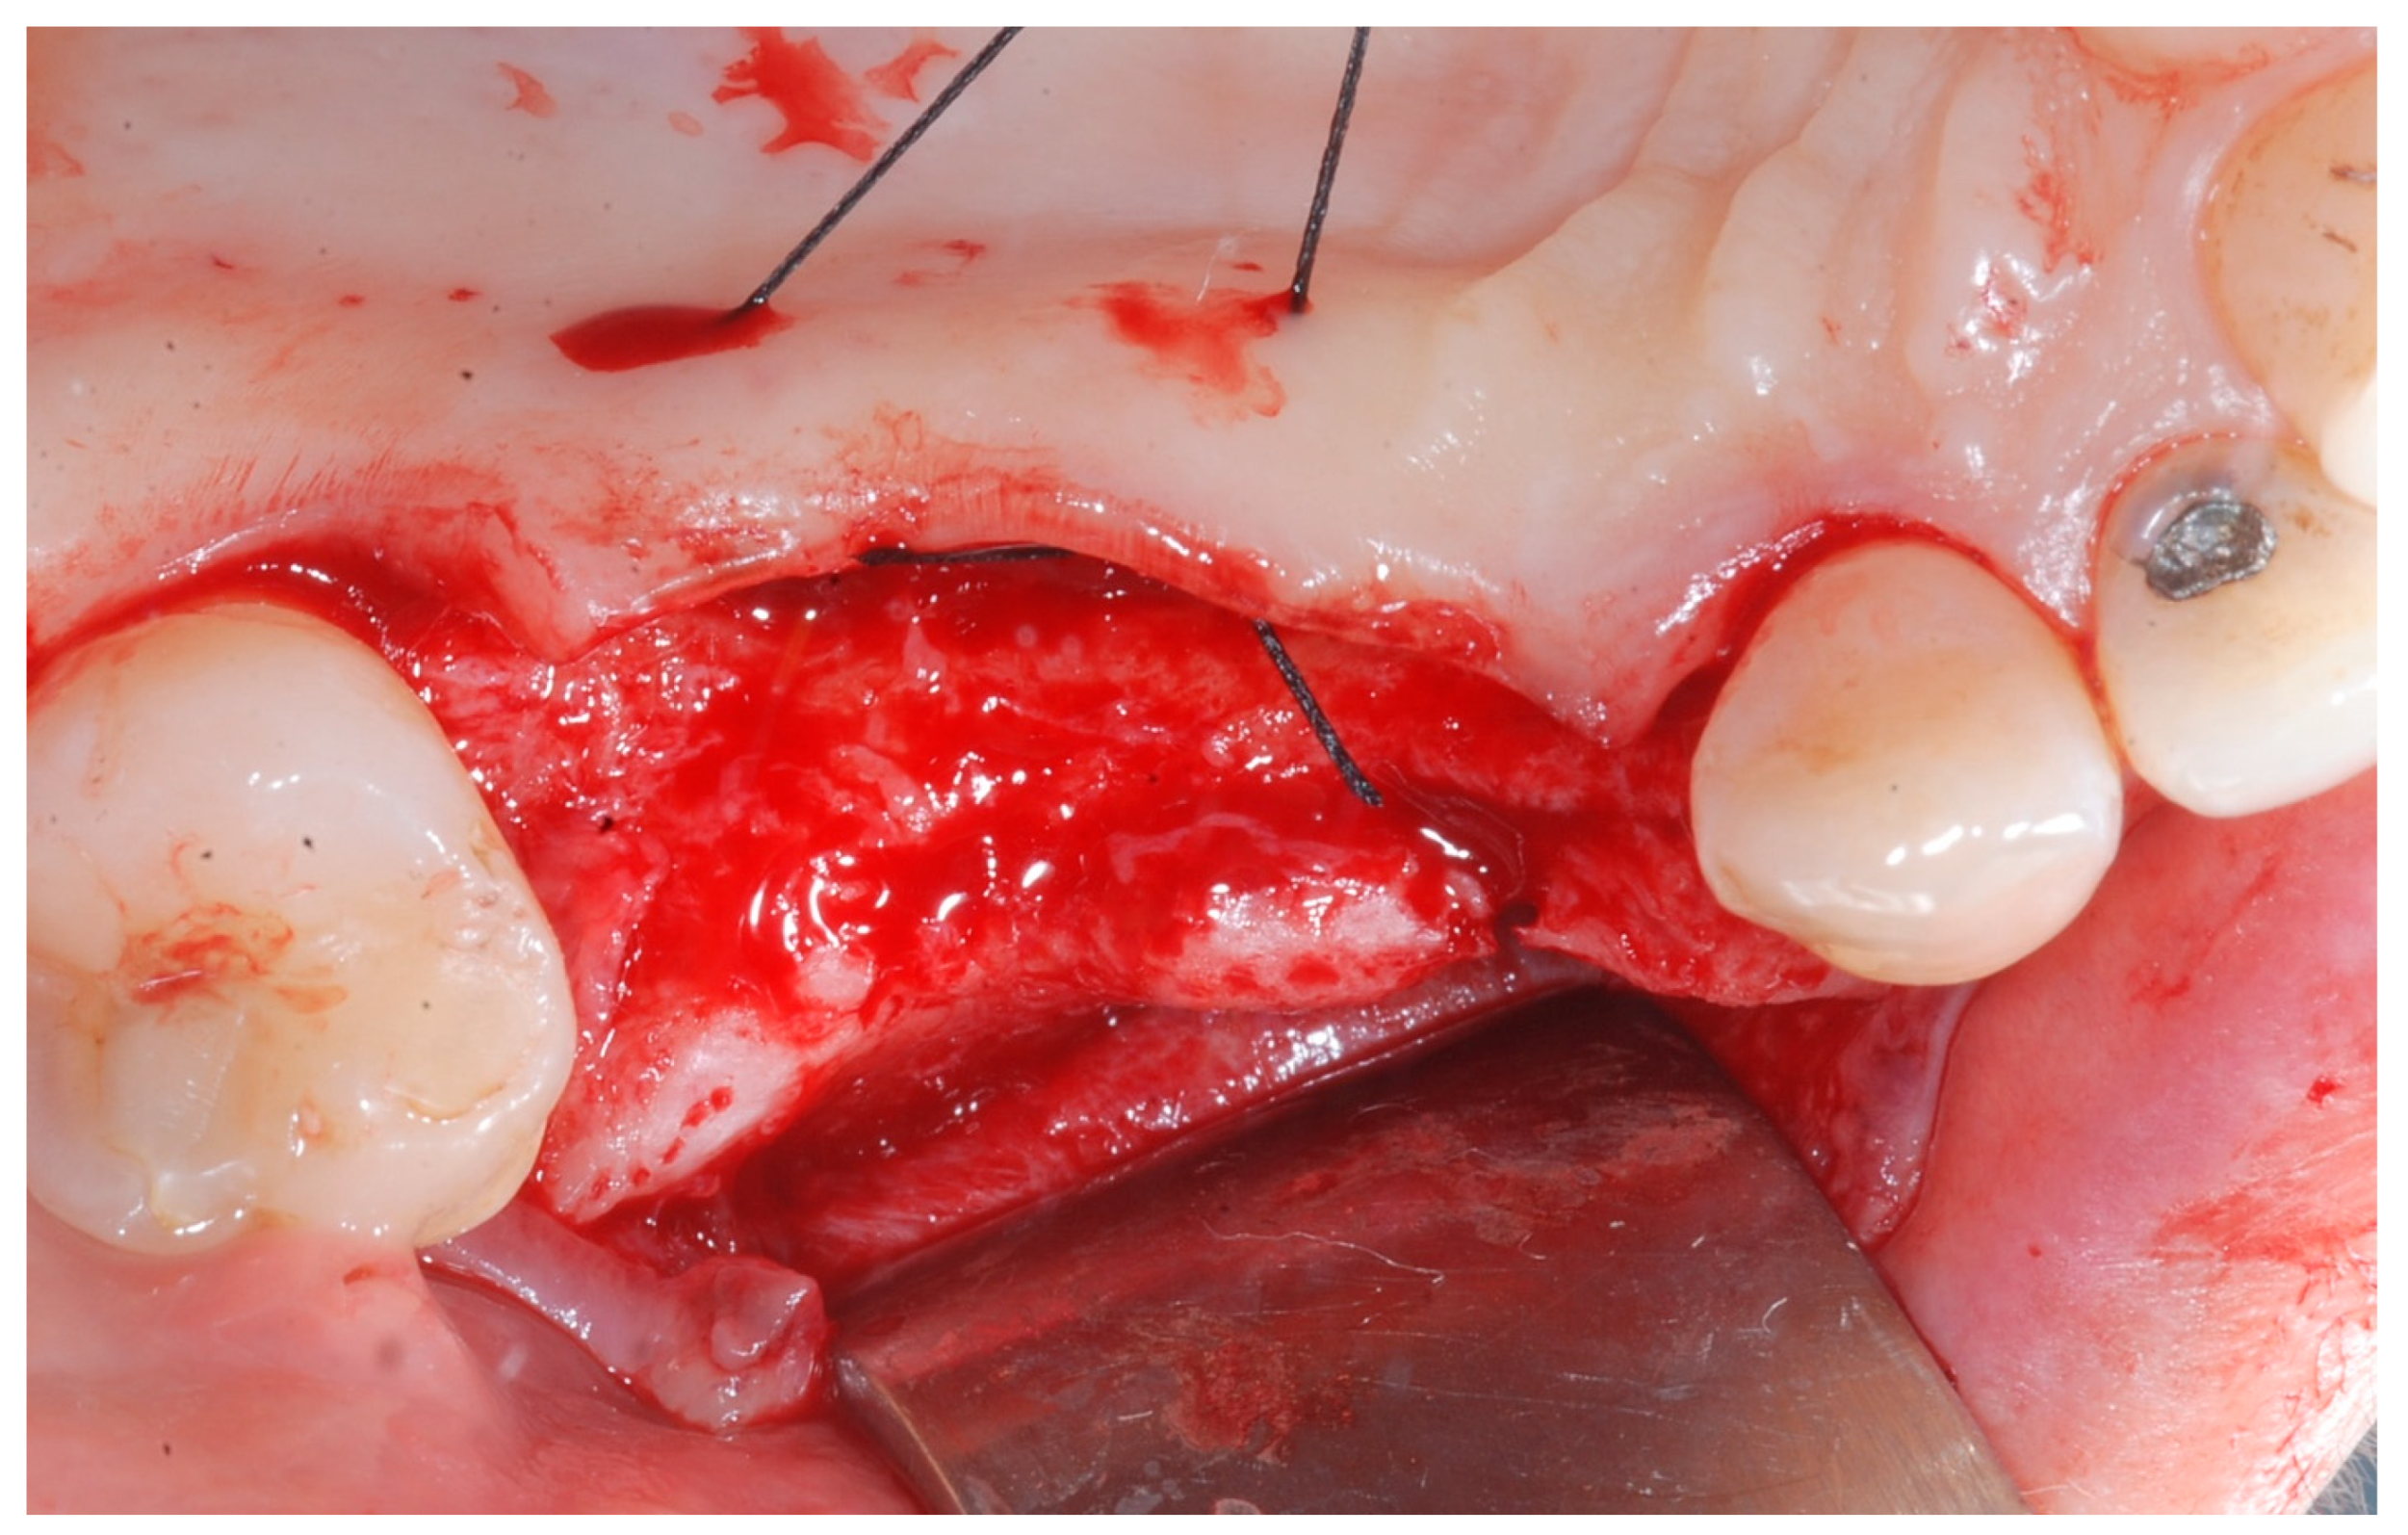

Six months following augmentation, re-entry surgery was carried out to uncover the implants and connect the healing abutments. Following chlorhexidine rinses and the injection of local anesthetics, crestal incisions as well as releasing incisions along the same lines as the ones during augmentation surgery were performed. Mucoperiosteal flaps were raised in order to visualize the augmented bone volume (Figure 9 and Figure 10).

During the 6-month period from T0 to T1, healing proceeded uneventfully in all patients, with no major complications or biocompatibility issues. No allergic reactions were observed. No complications such as flap dehiscence, membrane exposure, wound infection, fistulae with pus discharge, or foreign body reactions were noticed. None of the surgical sites had to be re-opened earlier. During the re-entry phase, in each surgical site no membrane remnants could be detected. Augmented newly formed hard tissue was observed clinically, with macroscopic features of healthy, bleeding, newly formed bone. Remnants of DBBM granules were occasionally visible and appeared firmly attached to the regenerated hard tissue, with no macroscopic signs of fibrous encapsulation. A thin layer of pseudo-periosteum with a thickness < 1 mm was seldomly observed. In all cases, implants appeared clinically stable, with no residual bony dehiscences or fenestrations at the buccal aspect.

Figure 9. Reopening surgery showing no membrane residues and obtained buccal bone thickness.

Medicina 61 01814 g009

Figure 10. Reopening surgery showing no membrane residues and obtained buccal bone thickness.